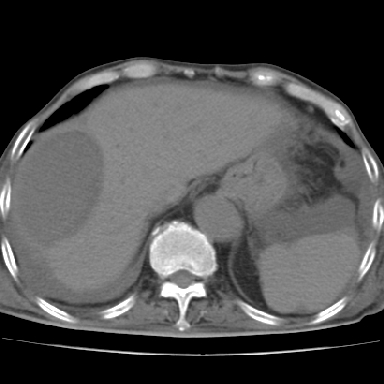

以下是引用qian在2006-12-4 19:11:00的发言:[br]胸腔和腹腔内均见有液性影,肝上极包膜下有一较大椭圆形低密度影,密度均匀,边缘清晰,结合病史考虑术后肝脓肿并胸腹腔积液。

以下是引用chry3在2006-12-4 21:05:00的发言:[br]应该往上扫几层,我考虑膈下脓肿。[br]大家考虑:胃部手术怎会造成肝内脓肿,隔下脓肿到是会造成的

以下是引用dyqct在2006-12-4 19:54:00的发言:[br]考虑:1、肝包膜下脓肿;[br] 2、少量腹水;[br] 3、右侧少量胸膜腔积液。